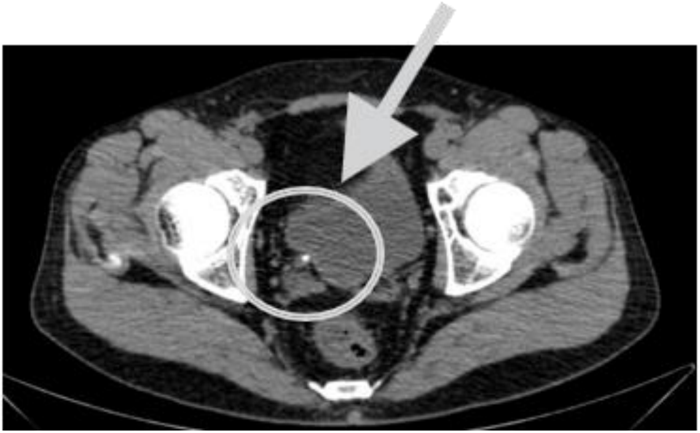

Homem, 42 anos, queixa de dor em fossa ilíaca direita de forte intensidade de início súbito associada a náusea sem vômitos há 2 horas, com irradiação para região inguinal ipsilateral, sem fatores de piora ou melhora. Ao exame físico, abdome flácido, leve desconforto à palpação de fossa ilíaca direita, sem plastrão palpável ou tumefações subcutâneas. Sinais de Blumberg e Giordano negativos. Foi medicado e apresentou alívio da dor.

Hemograma com Hb 14,3 g/dL, Leucócitos 9580 s/ desvio. Proteína C Reativa 1,2 g/dL (normal <1,0). Urina I com hemácias 12 mil (normal <10 mil) e leucócitos 11 mil (normal < 10 mil), sem outros achados.

Após ver a tomografia e confirmar a hipótese diagnóstica mais provável para este caso, cite o próximo passo para o tratamento: